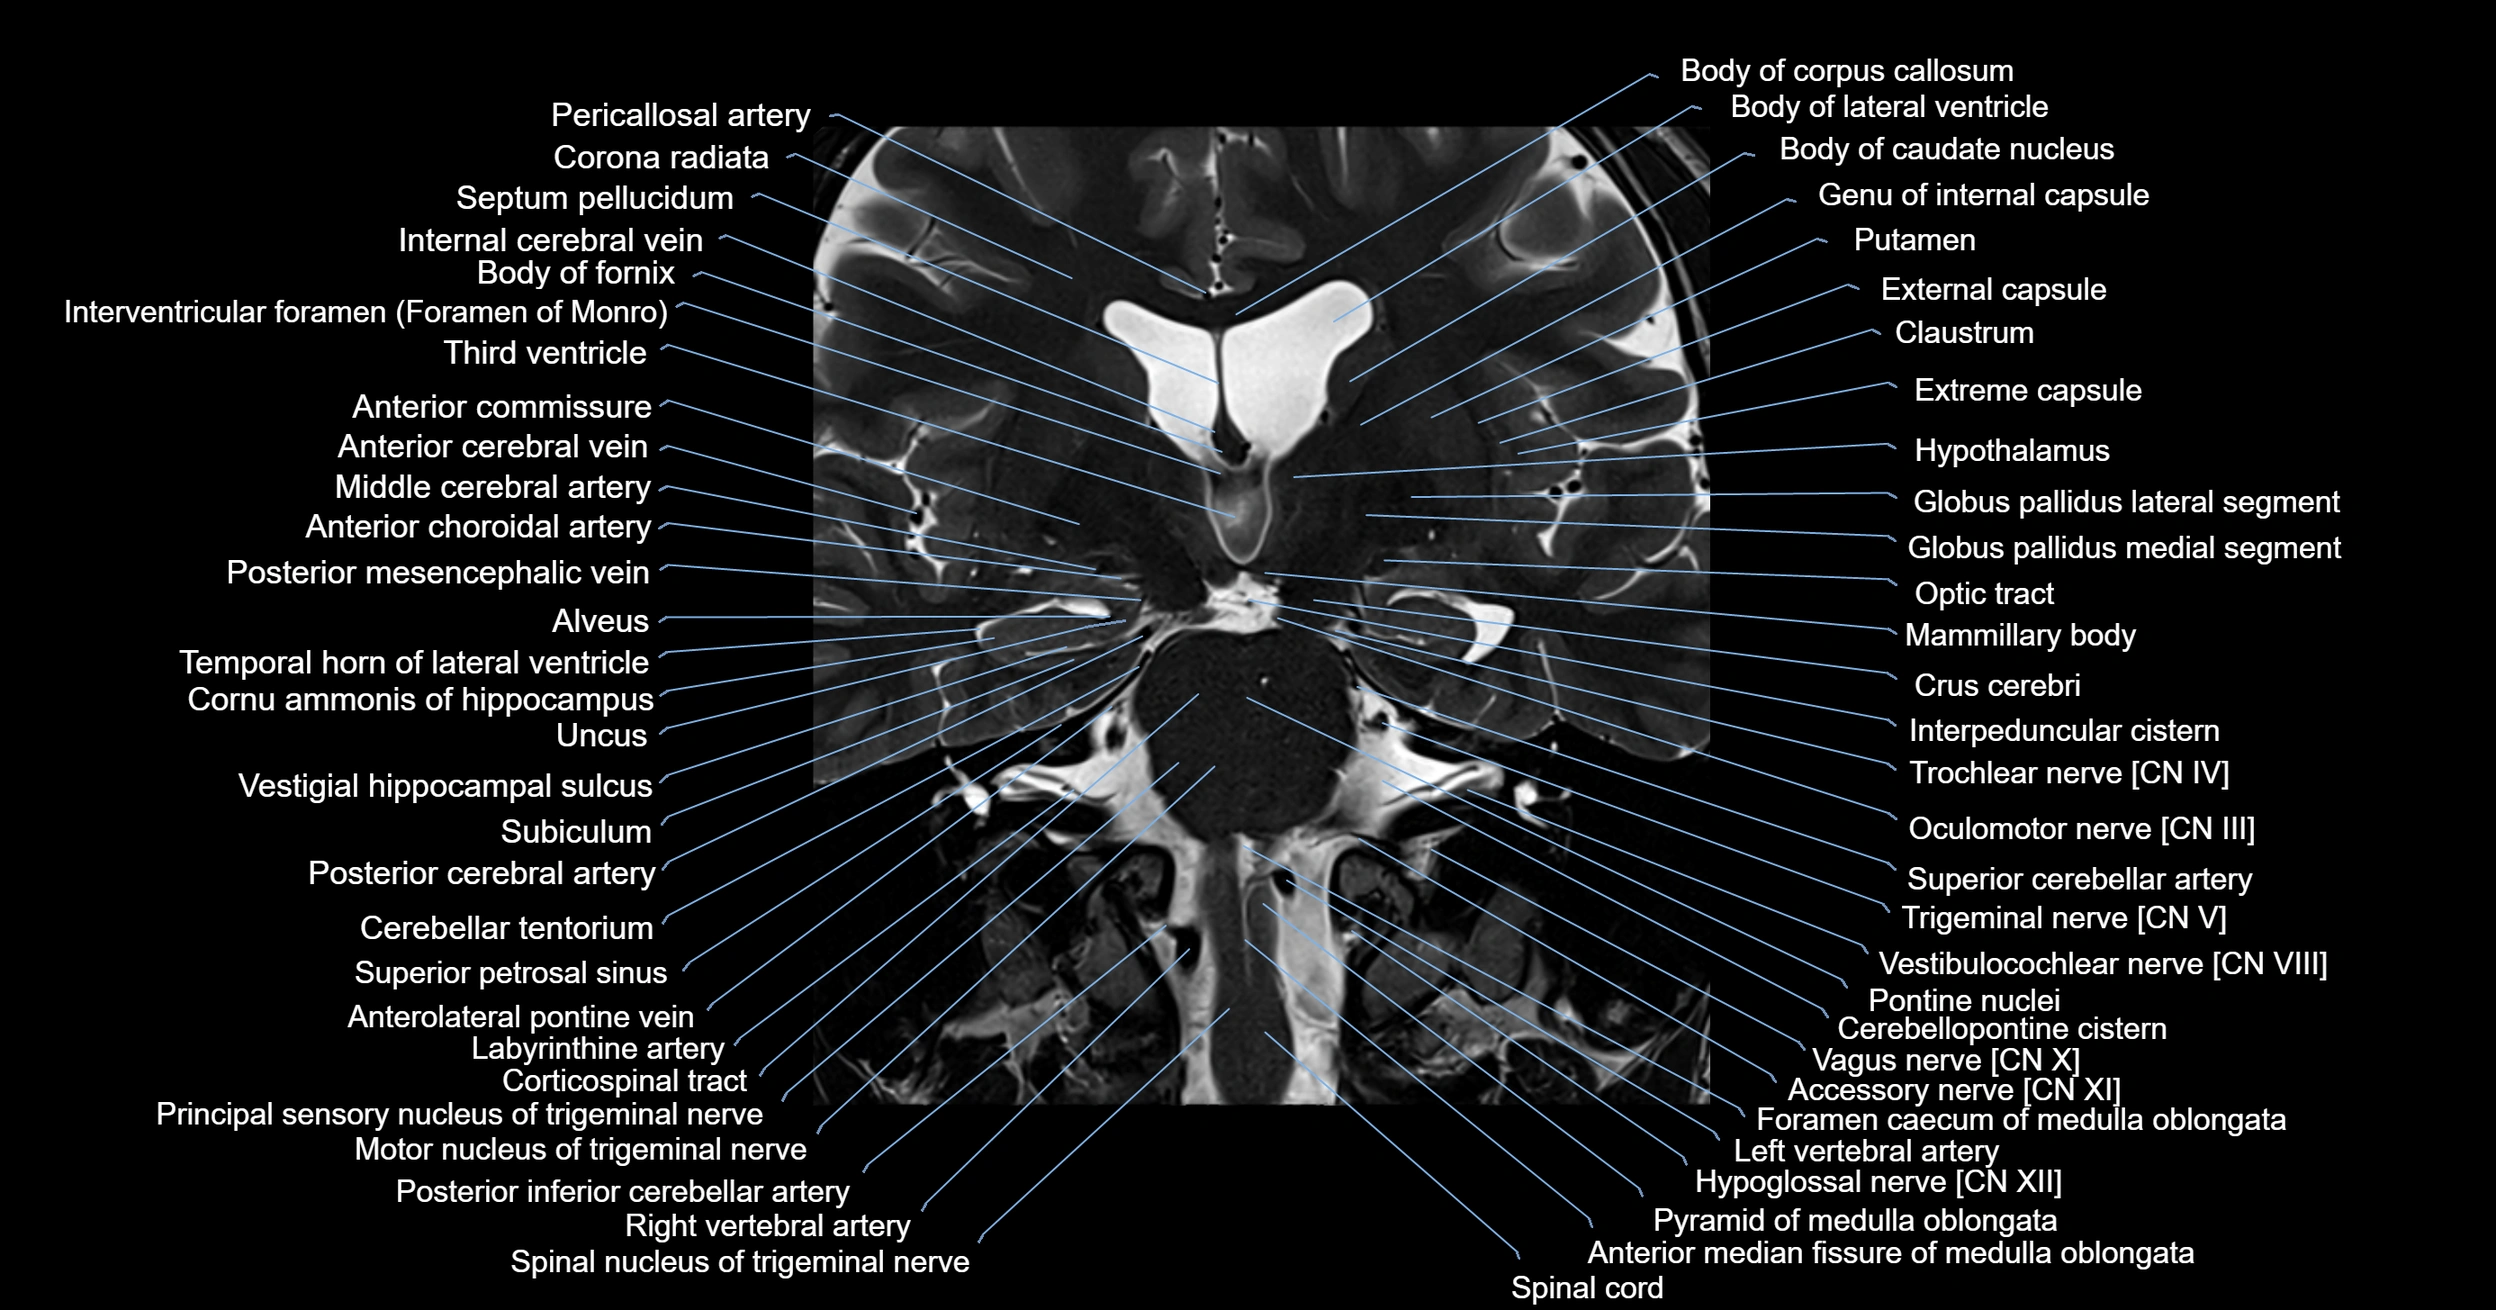

MRI images